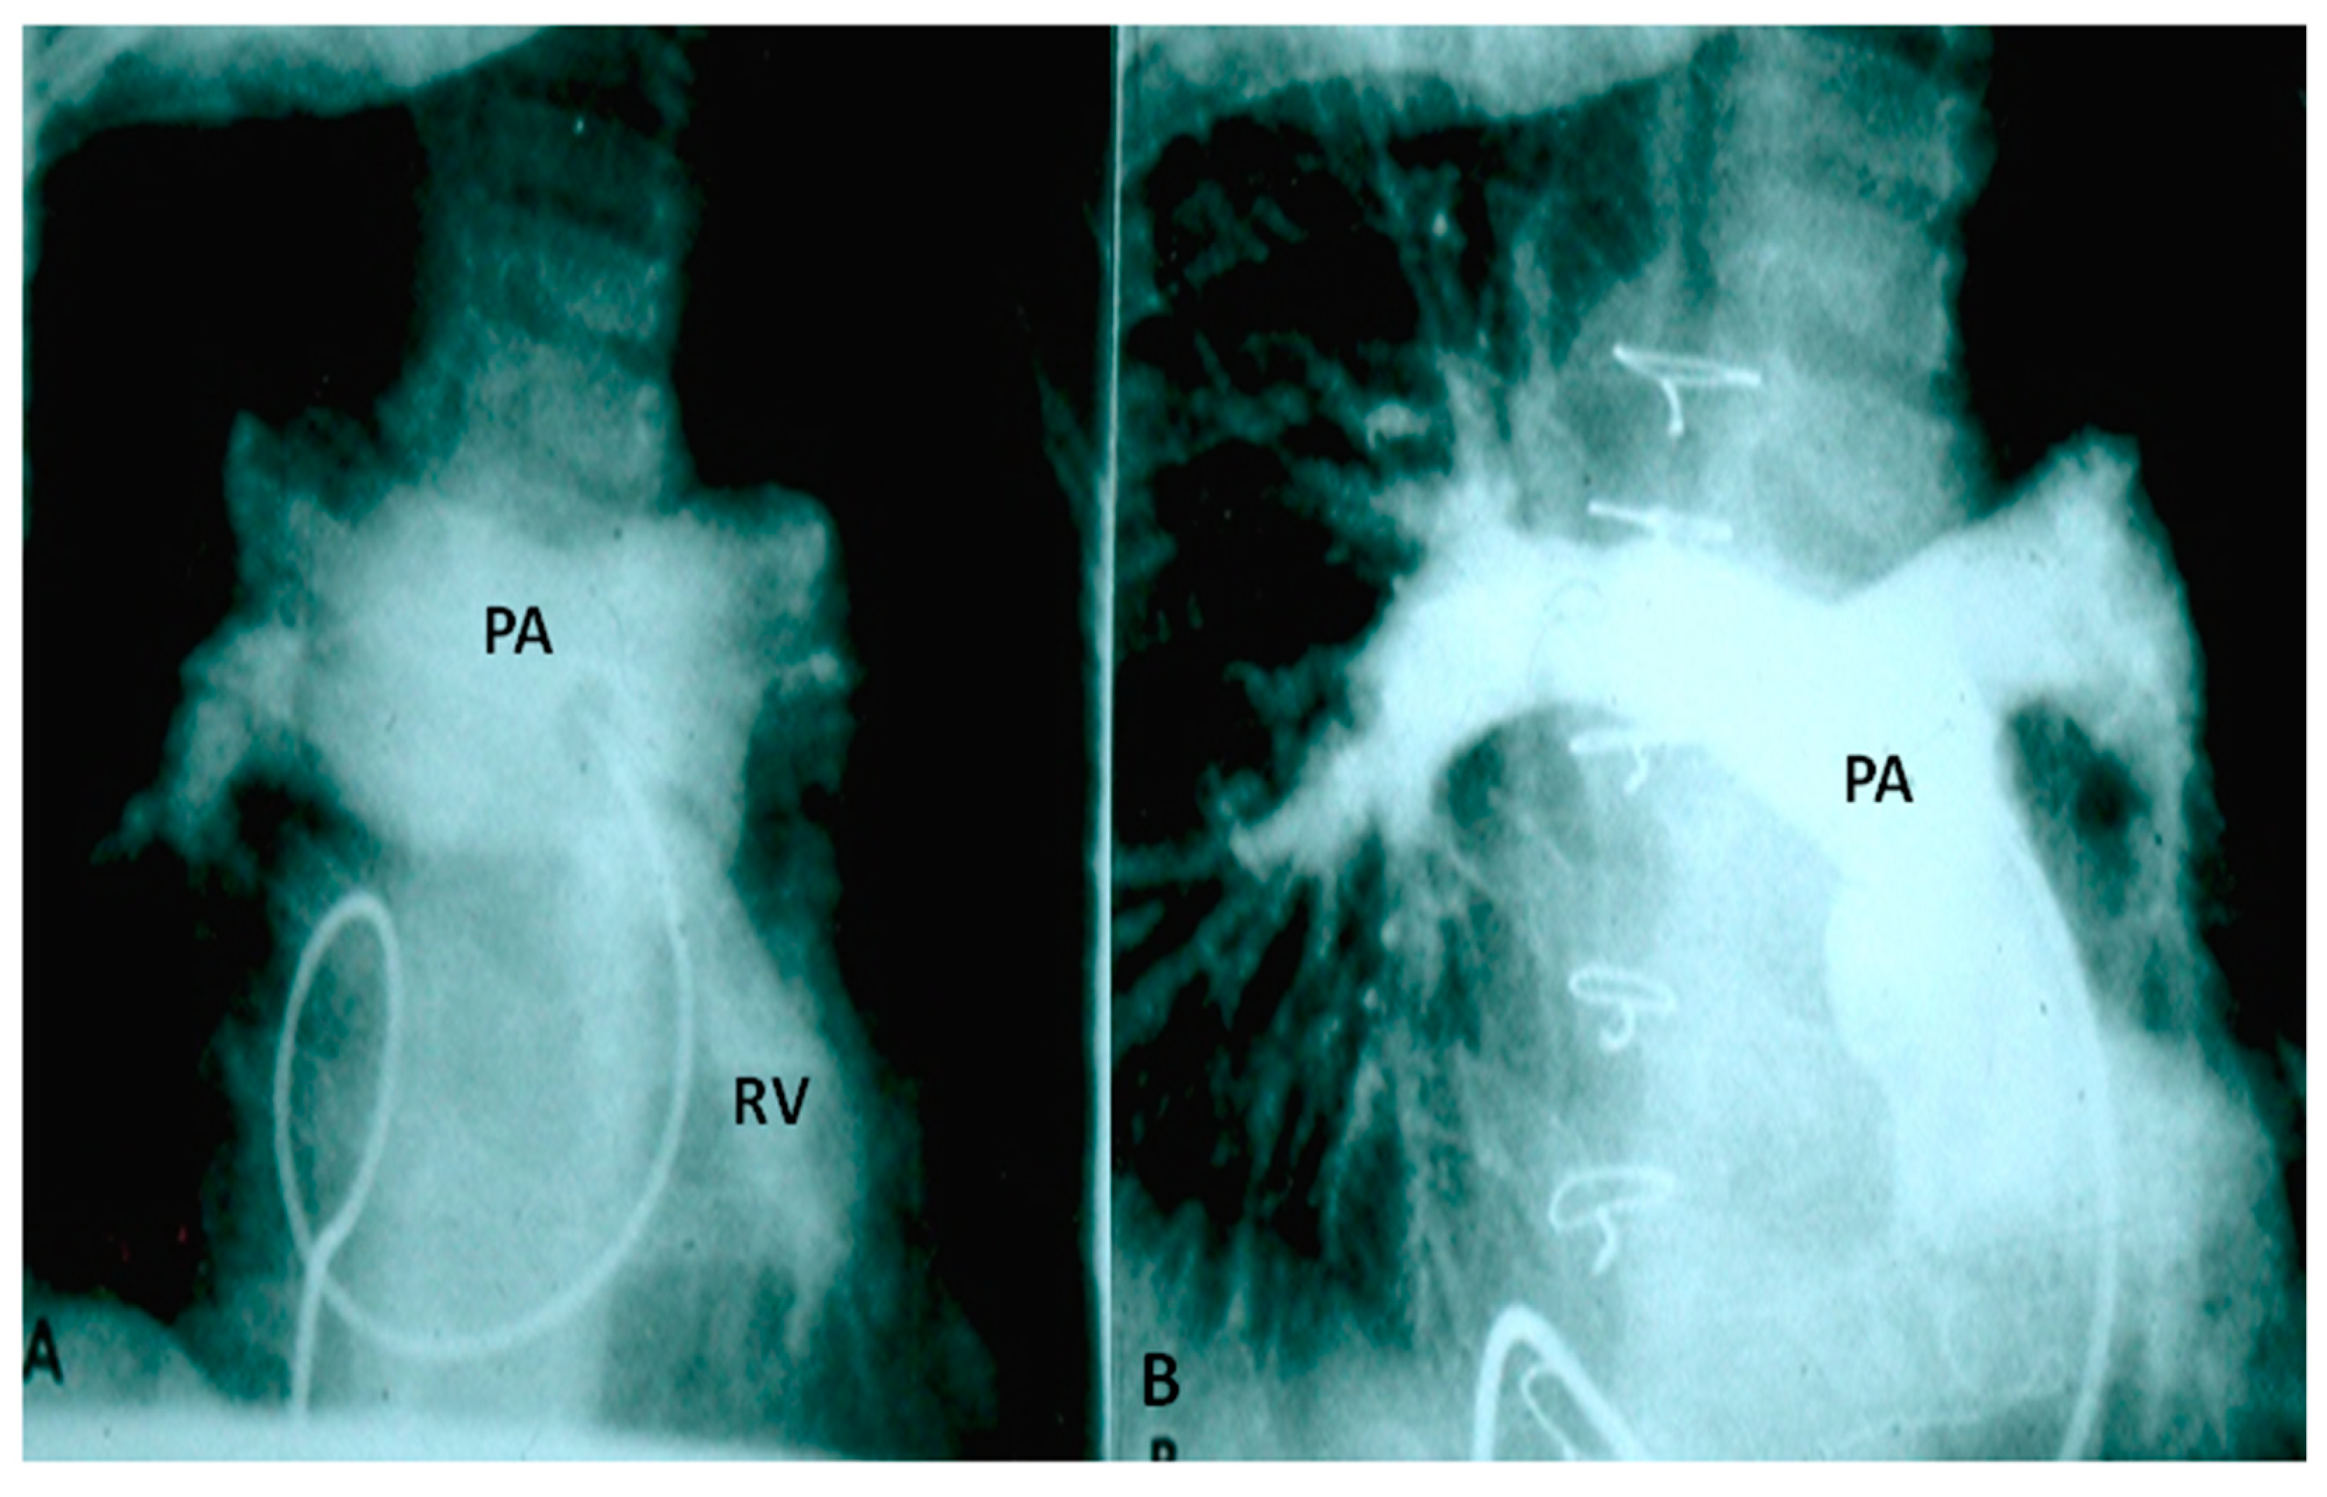

Two types of clinical presentations are recognized, neonates with severe respiratory distress and patients presenting beyond six months of life with little or no respiratory symptoms. In the first group, chest physiotherapy and ventilatory support to stabilize the baby, prone position to “move the pulmonary arteries away from the tracheobronchial tree,” and reduction of the PA pressures by pulmonary vasodilators such as nitric oxide (NO) may be helpful. Babies with severe respiratory distress may require emergency sternotomy to relieve the obstruction or place the patients on extracorporeal membrane oxygenation (ECMO) [4,5,35,36,37]. Anti-congestive measures are provided in babies who have obvious signs of CHF. Once the patient is stabilized, total surgical correction to include closure of VSD, relief of pulmonary stenosis by a trans-annular pericardial patch as necessary and partial resection and plastic repair of aneurismally dilated main and branch PAs (Figure 5) should be performed under cardiopulmonary bypass. Some controversy exists with regard to whether prosthetic replacement of the pulmonary valve is required at the time of primary repair [37,38]; the author’s opinion is that valve replacement may not be necessary in all cases at the time of primary surgery [37].